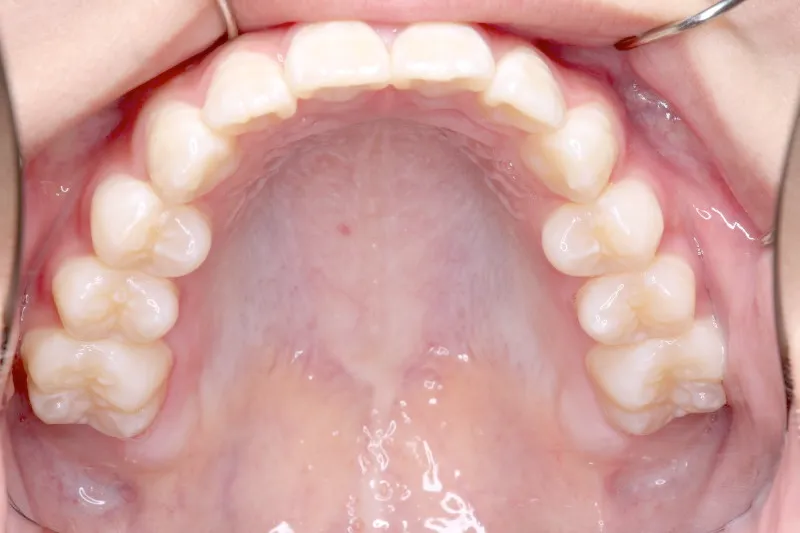

• 初診

初診時年齢 6歳まで (女性) 主訴 ガタガタ

診断名 叢生 装置名

状態 永久歯が生える隙間がない(叢生)

ガタガタ・でこぼこに生えている(叢生)

下の歯がずれて生えています。

こどもの歯は下の2本しか抜けていませんが、放っておくとガタガタがきつくなるので、早い段階からの治療としました。